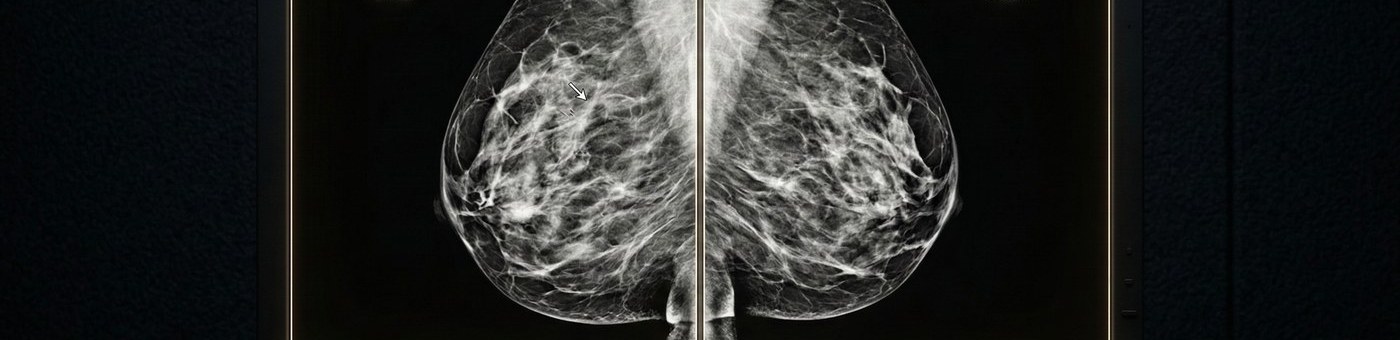

2D and 3D Tomosynthesis Reads

We interpret both conventional 2D digital mammography and 3D digital breast tomosynthesis (DBT) — including combo mode studies (2D + 3D acquired together). Our readers are experienced on GE, Hologic, Siemens, and Fujifilm mammography systems.